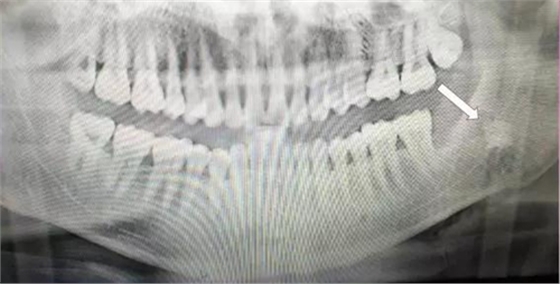

下面看一個(gè)病例,患者,女,30歲,因左下頜智齒嵌塞食物后疼痛,至當(dāng)?shù)匮揽平o予拔除,但術(shù)后1個(gè)半月,患者自覺(jué)拔牙區(qū)一直隱隱疼痛,時(shí)輕時(shí)重,遂來(lái)診。檢查發(fā)現(xiàn),拔牙創(chuàng)口一直未愈合,未見(jiàn)明顯腫脹,拍片發(fā)現(xiàn),拔牙窩內(nèi)顯示高密度斷根影

像,該斷根臨近下頜神經(jīng)管,同時(shí)發(fā)現(xiàn)第二磨牙遠(yuǎn)中有兩塊高密度影像,疑似殘留骨片或牙片,應(yīng)該是引起疼痛的原因,經(jīng)與患者溝通,采納建議,進(jìn)行二次拔牙。